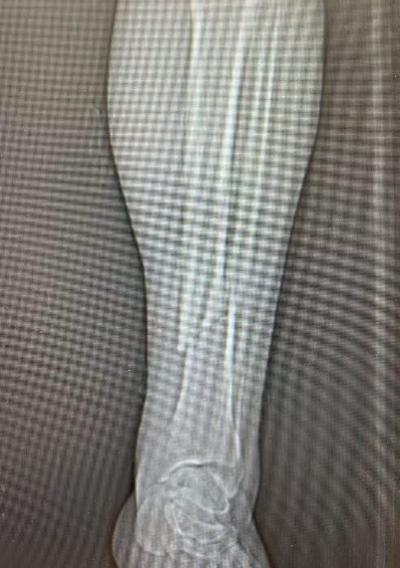

10月4日,59岁张先生不慎被他人电瓶车撞伤致左踝、左小腿疼痛,来院就诊后,王建伟医师团队为患者实行“左胫骨骨折切开复位内固定术”